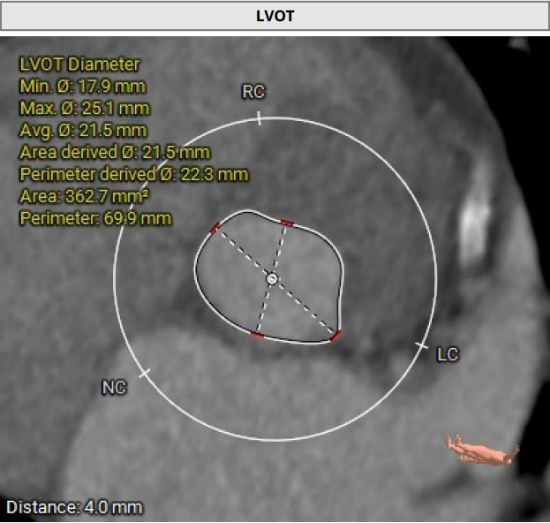

主动脉瓣瓣环及其他基本平面测量

主动脉瓣瓣上及瓣下多平面测量

经过医院多学科团队术前测量对病例深入分析,同时结合AI术前分析辅助决策软件进行三维和二维图像融合结果,指出本例难点/要点主要包括:

• 三叶式主动脉瓣,轻度钙化,瓦氏窦较小(直径约26-28mm),应注意瓣膜、预扩和/或者后扩球囊型号的选择;